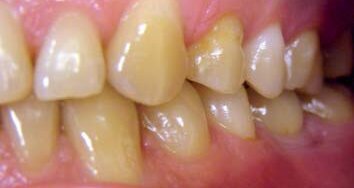

Niniejszy artykuł przedstawia przypadek 38-letniej pacjentki, skierowanej z Wydziału Ortodoncji do Kliniki Stomatologicznej studiów podyplomowych na Wydziale Chirurgii Stomatologicznej na Uniwersytecie Arystotelesa w Salonikach. Powodem skierowania było niestosowanie się do zaleceń wynikających z leczenia ortodontycznego (Ryc. 1). Z tej przyczyny podjęto szybsze i zachowawcze leczenie estetyczne zębów odcinka przedniego. Zęby przednie mają znaczący wpływ psychologiczny i emocjonalny na pacjentów ze względu na ich widoczność w uzębieniu oraz rolę, jaką dogrywają w uśmiechu.

Pacjentka narzekała głównie na kolor oraz przerwy między zębami w odcinku przednim górnego łuku (Ryc. 2-6). Po zebraniu wywiadu medycznego oraz stomatologicznego wykonano badanie kliniczne i radiologiczne w celu ustalenia rodzaju problemu (związek z próchnicą, problem natury periodontologicznej lub endodontycznej).

Podczas wywiadu stomatologicznego pacjentka przyznała, że miesiąc wcześniej leczono ją periodontologicznie i że pozostała pod obserwacją na Wydziale Periodontologii. Co więcej, wspomniała, że nosiła aparat ortodontyczny przez ponad 5 lat i że nie chciała kontynuować leczenia. Ortodonta stwierdził, że pacjentka nie była współpracująca, jeśli chodzi o wymianę ligatur oraz że nie pojawiła się na kilku wizytach mimo odklejonych zamków, nie utrzymywała też wystarczającej higieny jamy ustnej. Dodatkowo, oczywistym było przeciwwskazanie do kontynuacji leczenia ortodontycznego ze względu na ryzyko resorpcji korzeni spowodowane długotrwałą aktywacją aparatu.

Badanie kliniczne wykazało niski poziom higieny jamy ustnej, przerost dziąseł, widoczne przebarwienia wokół zamków z powodu palenia tytoniu, próchnicę w prawym górnym kle oraz koronę na metalu na zębie 22 (Ryc. 2-6). Po zdjęciu zamków wykryto niewielka demineralizację szkliwa wokół nich. Zauważono też przesunięcie linii pośrodkowej łuku górnego w stosunku do linii pośrodkowej twarzy (Ryc. 1). Badania kliniczne i radiologiczne nie wykazały nieprawidłowości w odcinkach bocznych.